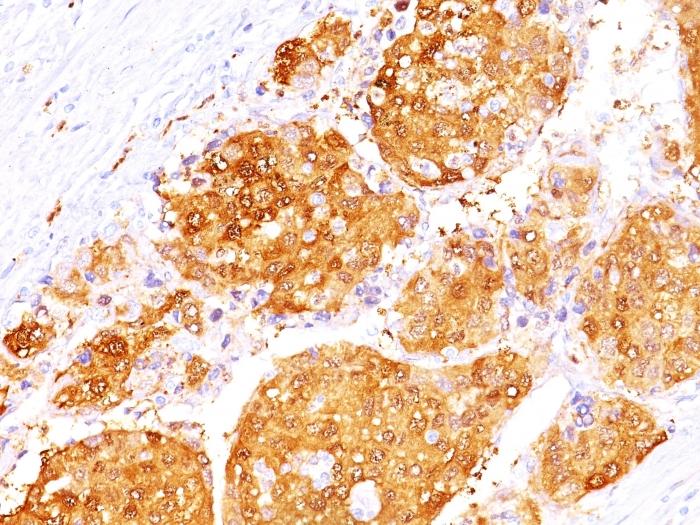

This antibody recognizes a protein of 35-38 kDa, which is identified as Arginase 1 (ARG1). Arginase is a manganese metallo-enzyme that catalyzes the hydrolysis of arginine to generate ornithine and urea. Arginase I and II are isoenzymes which differ in subcellular localization, regulation, and possibly function. Arginase I is a cytosolic enzyme, which is expressed mainly in the liver as part of the urea cycle, whereas arginase II is a mitochondrial protein found in a variety of tissues. Antibodies to Arginase 1 label hepatocytes in normal tissues and granulocytes in peripheral blood. Arginase 1 is a sensitive and specific marker for identification of hepatocellular carcinoma.Primary antibodies are available purified, or with a selection of fluorescent CF® Dyes and other labels. CF® Dyes offer exceptional brightness and photostability. Note: Conjugates of blue fluorescent dyes like CF®405S and CF®405M are not recommended for detecting low abundance targets, because blue dyes have lower fluorescence and can give higher non-specific background than other dye colors.

Positive Control

293T cells. Hepatocellular Carcinoma (HCC).